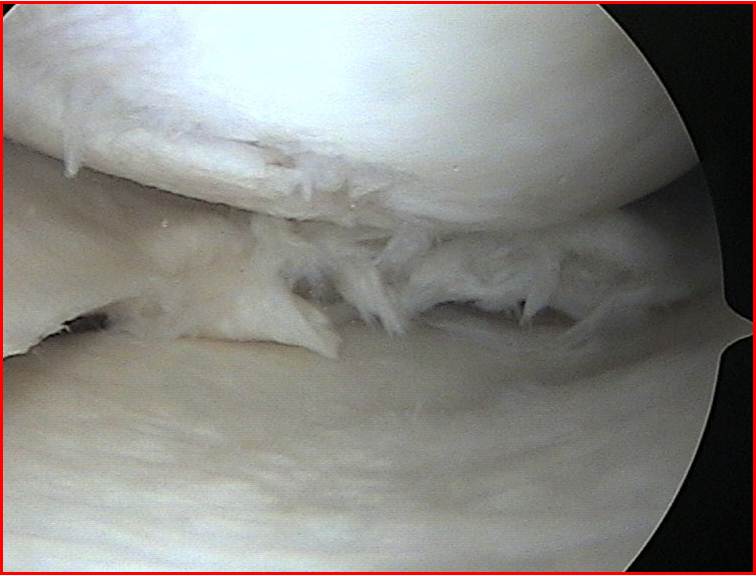

- Lesiones meniscales

- Lesiones cartílago articular

- Limpieza articular